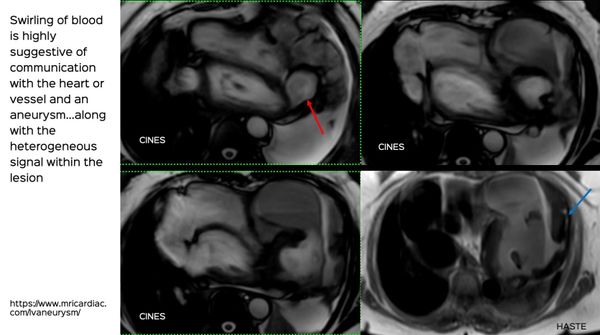

Multimodality Imaging of an LV Aneurysm

A complex long-standing, slow growing LV aneurysm